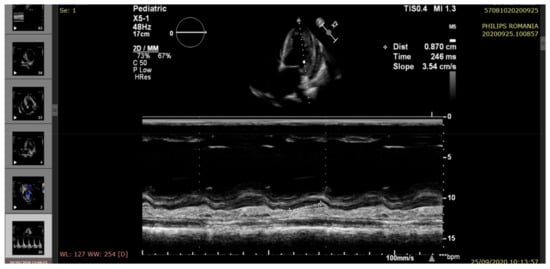

| Right ventricular ejection fraction RV EF (%) | >60 | 55 | 50 | 55 | 45 |

| Left ventricular ejection fraction LV EF (%) | >60 | 60 | 35 | 45 | 25 |

| (S’) Lateral systolic myocardial velocity (cm/s) tissue doppler imaging (TDI) | 8.43 ± 1.06 | 10.5 | 7 | 8.7 | 5.9 |

| Mitral annular plane systolic excursion (MAPSE) (mm) (M-mode) | 16.4 ± 2.4 | 15 | 9.2 | 12.2 | 8.3 |

| Mitral diastolic pattern | Normal | Impaired relaxation | Pseudonormal filling | Impaired relaxation | Restrictive filling |

| Pericardial fluid (edge) | <5 mm | Small (6 mm) | Raised (20 mm) | Moderate (14 mm) | Large (22 mm) |

| Pulmonary hypertension (echocardiographic criteria) | Normal | Mild | Moderate | Mild | Moderate/severe |